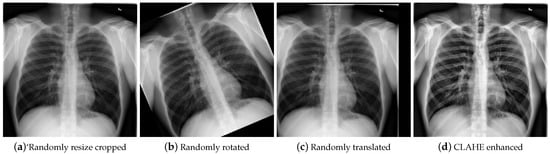

- Resizing: Random size cropping is performed on the images, followed by resizing them to 224 × 224 pixels. This provides a consistent data foundation and enhances the robustness of the model to different perspectives and scales through the randomness of cropping (see Figure 5a). Random cropping is a basic data augmentation method that has been widely used [45].

- Rotation and translation: Random rotation and translation are applied to simulate changes in shooting angles in real-world scenarios, improving the applicability and accuracy of the model (see Figure 5b,c). Studies have shown that random rotation and translation significantly enhance the performance of the model in handling data with different shooting angles [46].

- CLAHE image enhancement: Contrast-limited adaptive histogram equalization (CLAHE) is used to improve image contrast, which is particularly suitable for CXR images, significantly enhancing image quality and better supporting model training (see Figure 5d). This method has been widely validated as effective in medical imaging [47].